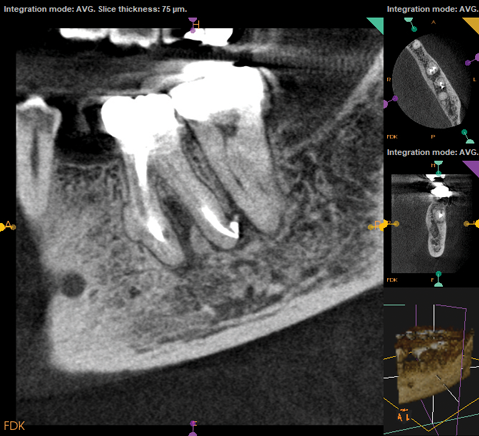

Fig 1. NSRCT can have high success, even with risk factors like periapical pathology associated, as depicted in this case presentation. Fig 1: Preoperative periapical radiograph showing AP. Fig 2: Preoperative CBCT. Fig 3: Immediate postoperative periapical radiograph. Fig 4: Three-month follow-up CBCT showing reduction of periapical radiolucency. Fig 5: One-year follow-up periapical radiograph showing resolution of periapical radiolucency.

Fig 1 through Fig 5. NSRCT can have high success, even with risk factors like periapical pathology associated, as depicted in this case presentation. Fig 1: Preoperative periapical radiograph showing AP. Fig 2: Preoperative CBCT. Fig 3: Immediate postoperative periapical radiograph. Fig 4: Three-month follow-up CBCT showing reduction of periapical radiolucency. Fig 5: One-year follow-up periapical radiograph showing resolution of periapical radiolucency.

Fig 4. NSRCT can have high success, even with risk factors like periapical pathology associated, as depicted in this case presentation. Fig 1: Preoperative periapical radiograph showing AP. Fig 2: Preoperative CBCT. Fig 3: Immediate postoperative periapical radiograph. Fig 4: Three-month follow-up CBCT showing reduction of periapical radiolucency. Fig 5: One-year follow-up periapical radiograph showing resolution of periapical radiolucency.

Just as systemic conditions and patient habits impact outcomes after NSRCT, the local dental environment and dental disease states also impact outcomes (Figure 1 through Figure 5). In the Toronto study evaluating 4- to 6-year outcomes following NSRCT, the presence of a periapical radiolucency emerged as a key prognostic factor, substantially reducing the success rate by a factor of four.12 Single-rooted teeth experienced better outcomes compared to multirooted teeth in the presence of periapical lesions.1 Teeth diagnosed preoperatively with irreversible pulpitis or necrosis, in the absence of AP, showed a more favorable prognosis compared to those with preoperative AP.2